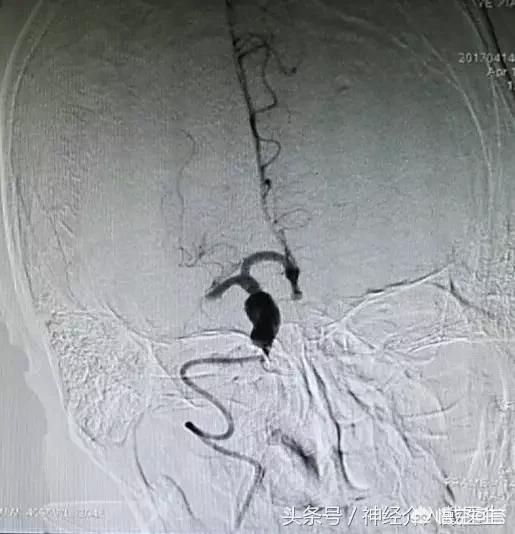

支架机械取栓治疗是目前治疗急性脑梗死的最为先进的技术手段,和溶栓治疗相比具有安全性高、作用显著和时间窗长等优点,目前已在国内外大型医疗中心普及。支架机械取栓是将一条直径0.3毫米左右的导丝从患者股动脉穿入体内,在透视监示下通过脑内大血管中的血栓进行定位,再用微导管将镍钛合金的取栓支架输送到血栓部位,释放支架后,镍钛合金支架自动膨胀展开,形成圆柱形网状结构,与血管壁贴合、嵌入血栓。术者将取栓装置抽离,栓子同时被拽出体外。